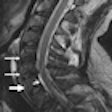

MRI of limited use in C-spine imaging of whiplash patients

January 11, 2012